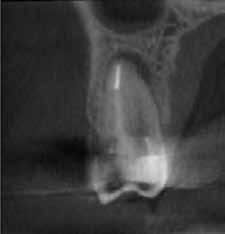

Krell és Caplan kutatásában 2086 repedt fogat vizsgáltak meg. A vizsgált fogak között leggyakrabban a második alsó nagyőrlőfogak (36%), majd ezt követően az első alsó nagyőrlők (27%), és végül az első felső nagyőrlők (18%) fordultak elő. A kutatási eredményeik szerint a fogbél állapota nem befolyásolta jelentős mértékben a kezelés várható kimenetelét. (Irreverzibilis pulpitis 85%; necrosis 80%; korábban gyökérkezelt 74%). A kimenetel szempontjából ugyanígy indifferens volt a páciensek neme, életkora, a kezelés időpontja, a fog pozíciója, a fog helyreállítása során használt anyag típusa, valamint az érintett fogfelszínek száma. 2014 júliusában egy 45 éves hölgy páciens azzal a panasszal kereste fel a rendelőnket, hogy nagyjából 10 napja egy fájdalmas duzzanat alakult ki a jobb felső első kisőrlője koronája mellett (14). A klinikai vizsgálat során egy amalgámtömést találtunk a panaszos fogban. A tömés széli zárása nem volt megfelelő, a disztális záróléc és a tömés között rést tapasztaltunk. A fog disztobukkális és linguális felszíne mellett 8 mm-es csontos tasakokat mértünk. A periapikális felvételen az 14-es foggyökér disztális felszínének megfelelően vertikális irányú radiolucens felritkulást észleltünk. A klinikai vizsgálat során a mesiális zárólécet kettéválasztó törésvonalat detektáltunk (17–18. ábra). A fogszenzibilitás vizsgálata során negatív eredményt kaptunk. A páciensnek ismertettük az elérhető terápiás lehetőségeket: 1, a 14-es fog eltávolítása, majd a foghiány 3 tagú cementezett híddal történő pótlása; 2, a 14-es fog eltávolítása, kemény- és lágyszöveti augmentáció, majd implantátum behelyezése; 3, a 14-es fog gyökérkezelése, gyökértömése és ezt követően a csücsökborítást biztosító restaurátum készítése. Arra is felhívtuk a páciens figyelmét, hogy a 3. terápiás lehetőség választása esetén nem tudjuk a fogmegtartás sikerességét garantálni, de végül – főként anyagi okok miatt – mégis ezt a terápiás opciót választotta. Fontos megjegyezni, hogy a repedt fogak ellátási lehetőségeit a törésvonal mélysége, elhelyezkedése, lefutása nagyban befolyásolja. A kezelés megtervezése során a fog és a fogat körülvevő szövetek állapotával kapcsolatos számtalan különböző faktort kell egyidejűleg figyelembe vennünk. A gyökérkezelést követően a gyökértömést meleg vertikális kondenzációs technikai alkalmazásával készítettük el (19. ábra). A hozzáférési nyílást folyékony és hibrid kompozit tömőanyag segítségével zártuk. A zárás elkészítése során a dr. David Clark által kifejlesztett Bioclear matricarendszert alkalmaztuk. A 6 éves kontroll során készített (2020) röntgenfelvételen a csontos defektus telődése volt megfigyelhető. Ez is a parodontális defektus gyógyulását igazolta (20–21. ábra).

17. ábra: A 14-es fog gyökerének disztális felszíne mellett vertikális csontpusztulásra utaló jelek észlelhetőek. Klinikailag ezen a területen 8 mm mélységű tasakmélységet mértünk. – 18. ábra: A 14-es fog disztális zárólécének megfelelően törésvonal észlelhető, ugyanakkor a csücskök teljes szeparálódására utaló jelek nem láthatóak. Az amalgámtömés eltávolítását követően jól megfigyelhető volt a törésvonal teljes lefutása. – 19. ábra: A gyökértömés elkészítése során meleg vertikális kondenzációs technikát alkalmaztunk. A felvételeken oldalcsatornák jelenlétére utaló jelek is észlelhetőek. – 20–21. ábra: A 2020-ban készült kontrollfelvételeken jól látható a csontos defektus telődése. A radiológiai jelek alapján (jól lekövethető gyökérhártyarés) a parodontális ligamentumok regenerációját is vélelmezzük.